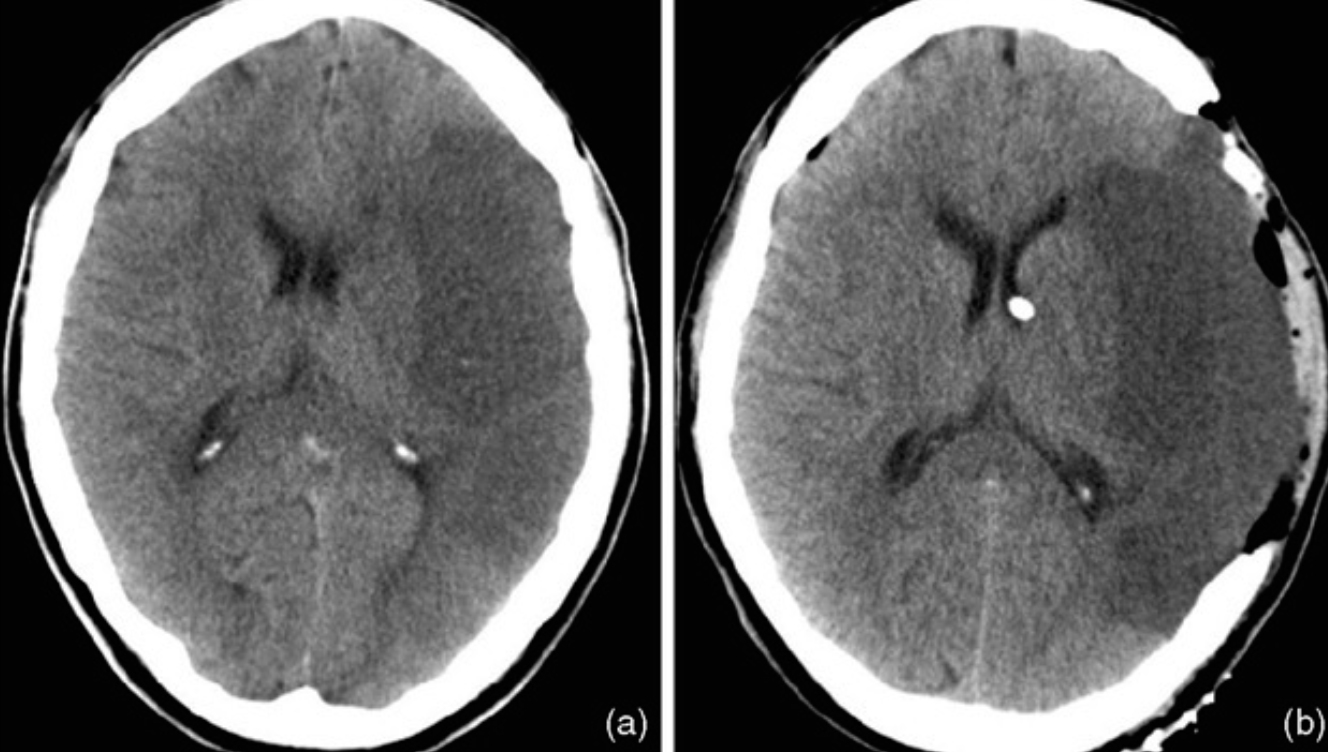

Axial CT scan obtained in a 57-year-old man who presented with left hemiplegia and obtundation.

Name the site of the lesion?

---basal ganglia---

What is commonest cause of this lesion?

---hypertension---